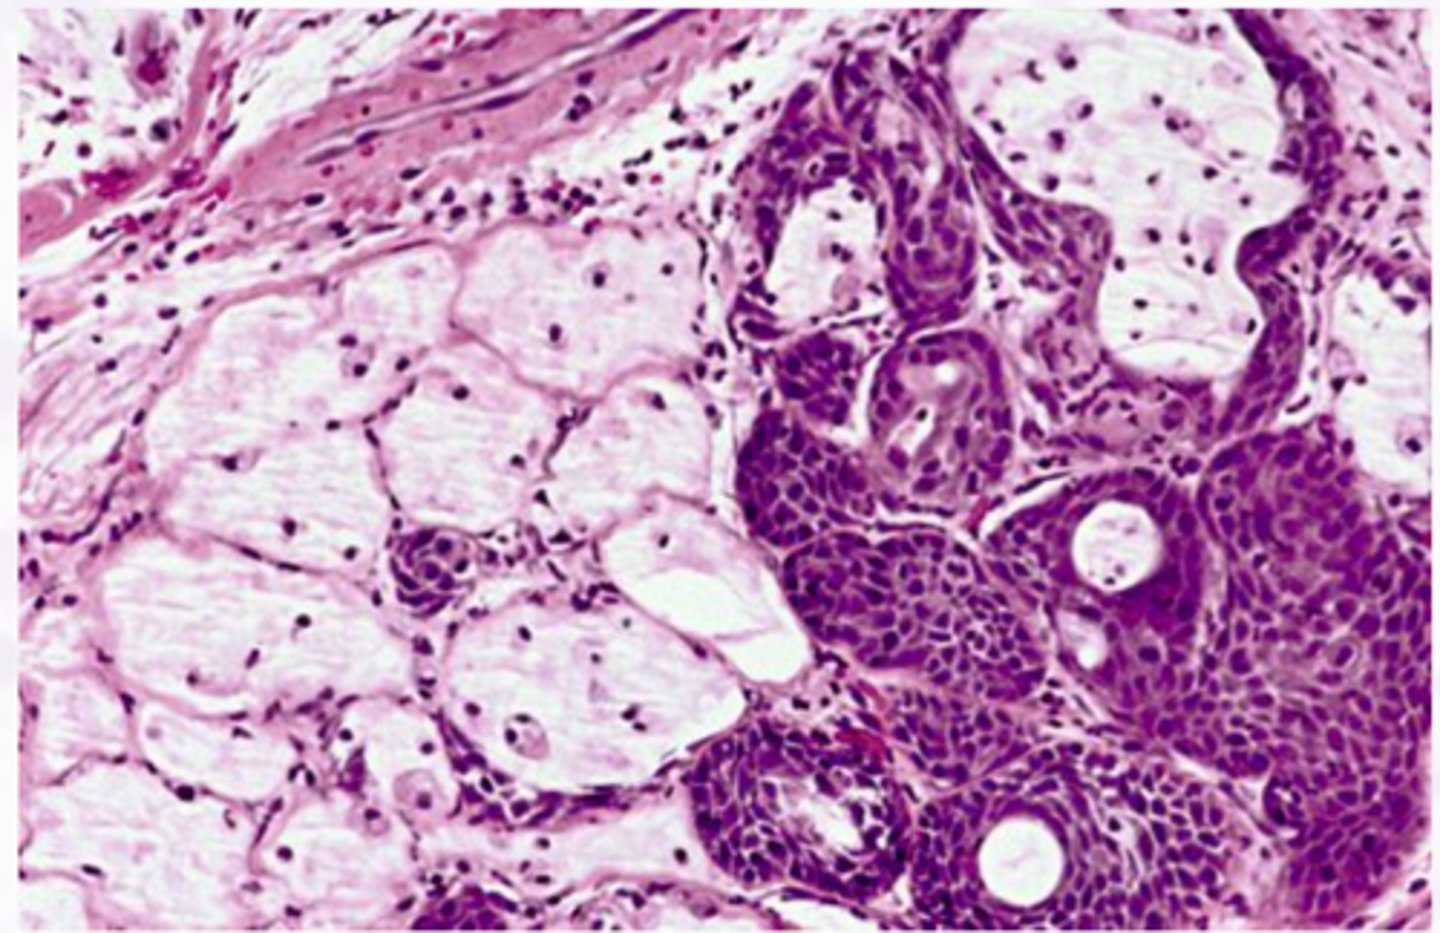

Adenoid Cystic Carcinoma

• Swiss Cheese pattern

▫ Islands with a

cribriform pattern

▫ Myoepithelial and ductal cells are present

▫ Perineural and perivascular invasion